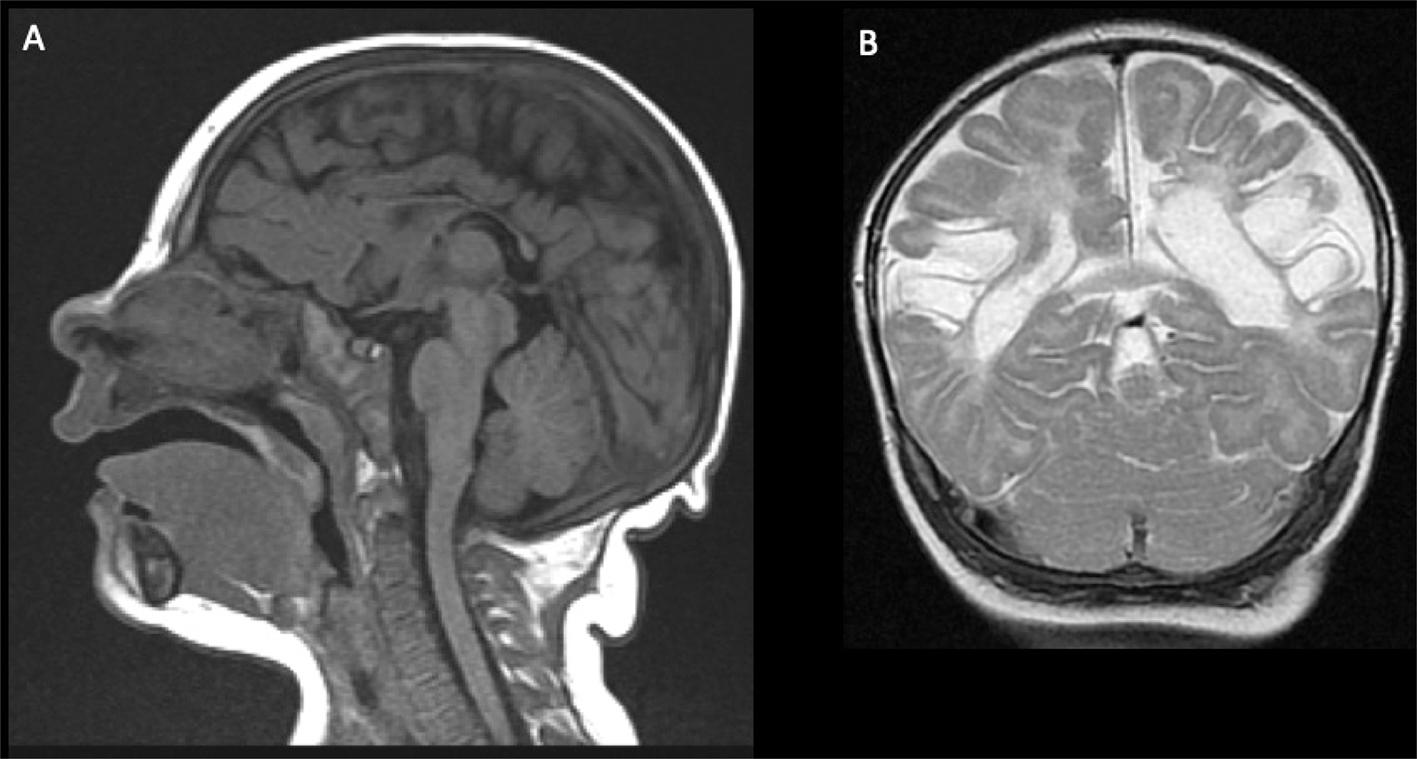

Acute phases of fetal stroke, such as in case of congenital heart disease or twin-twin transfusion syndrome (TTTS), may only rarely be detected prenatally. Fetal stroke often manifests with the chronic features of unilateral ventriculomegaly and volume loss with or without associated hemorrhage (Figures 1 and 2).

Fig 1

Figure 1. Acute and chronic fetal infarctions. 29 weeks of gestation fetus with a chronic stroke in the right hemisphere. (A) Axial HASTE (Half Fourier Singleshot Turbo Spin-Echo) and (B) Gradient Recall Echo (GRE) images showing unilateral enlargement of the right lateral ventricle, with periventricular white matter loss (white arrow) and linear blood staining (black arrowhead). 21 weeks of gestation fetus with congenital heart disease with acute stroke in the right hemisphere. (C) Axial DWI and (D) ADC map showing areas of reduced diffusion in the left ACA and MCA territories (black arrow) with questionable infarct in the right MCA territory (white arrowhead). Case courtesy of Dr. Tamara Feygin, Department of Radiology, Children’s Hospital of Philadelphia.

Fig 2

Figure 2. Three-day-old girl with chronic encephalopathy. Pregnancy complicated by maternal HELLP (H: Hemolysis, EL: elevated liver enzymes, LP: low platelet count) syndrome. Sagittal T1- (A) and coronal T2-weighted images (B) show microcephaly and bilateral chronic MCA-territory infarctions. Case courtesy of Dr. Tamara Feygin, Department of Radiology, Children’s Hospital of Philadelphia.